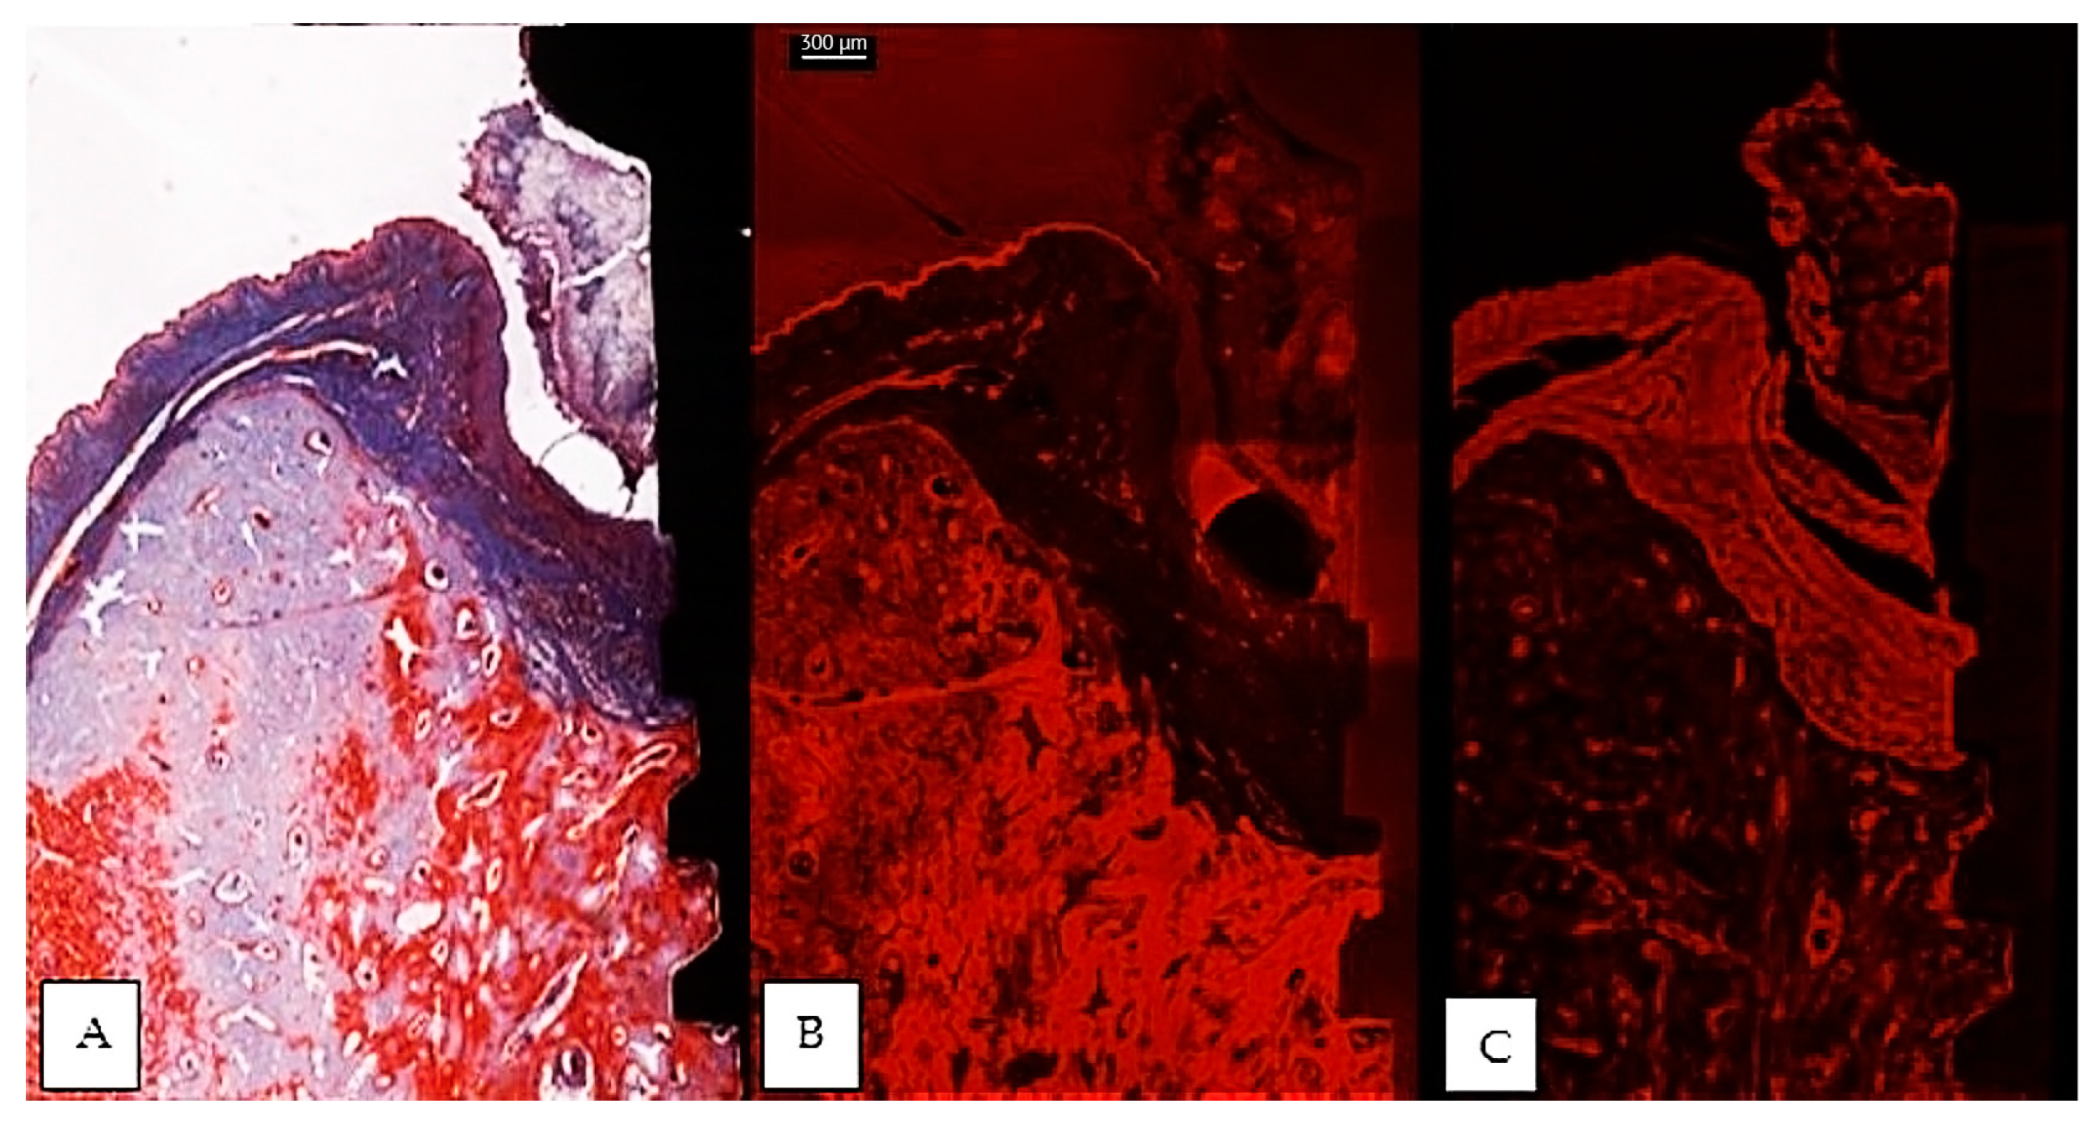

The usual light microscopy technique using pentachrome stains revealed good tissue morphology preservation; however, the opacity of the metallic implant made it difficult on some of the specimens to properly identify the implant shoulder. The CLSM thin sections were easier to scan, having a flatter surface, yet the grinding to a thin section led to minor tissue cracks in the bone component (Figure 3A,B). Furthermore, the use of mounting medium and coverslip on the thin sections induced an additional decrease in contrast, altering the quality of soft tissue morphology in the thin sections (Figure 3A,B). In both thin and thick sections, the implant shoulder was easily identifiable, except in the thick sections where the implant was lost during histological processing. The peri-implant sulcus is shallower in non-ligated specimens than in ligated ones, the bone is in contact with the implant surface and the soft tissue is in contact with the healing abutment (Figure 4). Infiltrated connective tissue (ICT) was present in contact with bone and implant (Figure 5). However, it is important to mention that the cellularity of the ICT was not visible under CLSM; therefore, LM seemed better suited for the assessment of the ICT. Epithelial lining integrity was broken, more pronounced on the oral aspect, making the identification of landmarks like aJE extremely difficult (Figure 6). This comes not as a surprise under the severe inflammation circumstances found in peri-implantitis, as this landmark is poorly identifiable even on LM. In these areas of integrity loss, the highly inflamed soft tissue was identified in direct contact with the bone and implant (Figure 7). Regarding the soft tissues, the epithelial covering is clearly identifiable on both types of evaluation (LM and CLSM).

Figure 3.

Comparative images of the same implant, between a thin section in light microscopy, Masson Goldner Anilin blue stain (A), same thin section in CLSM (B) and a thick section in CLSM (C). Morphological preservation of tissular integrity is better seen in the thick section. (implant #5, buccal aspect, bar measure for all three images is 300 µm).

In addition, the significant additional expense involved in the preparation of analyzable stained histological specimens and their susceptibility to errors need to be taken into account [54]. These findings must be considered critically, especially when preparing thinner stained sections. On the other hand, despite an increasing accuracy of the potentially visible histological details, very thin sections proved sometimes disadvantageous with respect to the handling of the specimens, the complexity of the fixation procedures and the duration of the grinding, and the creation of artifacts that could jeopardize the quality of the observations. In sections that are reduced to approx. 30 μm, scratches on the surface, extrusion of the implanted material, cracks, areas of sheer tissue loss, and uneven thicknesses may result in poor cellular detail, as noted in our study on the “thin” sections. [31] (Figure 3A,B). Many researchers agree that great technical skills are needed in obtaining satisfactory thin sections by maintaining parallelism during the grinding procedures. It is also known that during grinding the hard metal normally is depressed more on the sandpaper than the adjacent softer tissue, and this causes the surrounding tissue to abrade faster than the metal. Yet, the undecalcifed technique has been used widely for oral implants [55,56,57,58], despite the fact that processing artifacts in the histological very thin sections are still common [55].

The following supporting information can be downloaded at: https://www.mdpi.com/article/10.3390/jcm12072462/s1, VideoFile No. 1: 3D reconstruction of the non-ligated implant #4, on the buccal aspect; VideoFile No. 2: 3D reconstruction of the ligated implant #5, on the oral aspect; Figure 3 Comparative images of the same implant, between a thin section in light microscopy, Masson Goldner Anilin blue stain (A), same thin section in CLSM (B) and a thick section in CLSM (C).